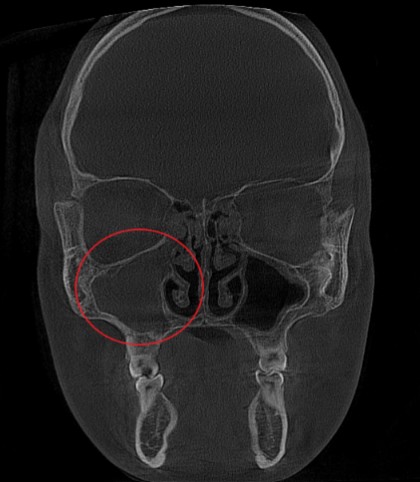

Проведена компьютерная томография околоносовых пазух, которая подтвердила наличие правостороннего гемисинусита (воспаление нескольких пазух с одной стороны), как следствие периодонтита зуба 1.6.

Представлено КЛКТ околоносовых пазух до начала лечения. Выделена зона воспаления пазух.